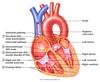

outline the route of the mammalian respiratory system

pharynx, larynx, glottis

trachea, bronchi, LUNGS: bronchioles, alveoli- squamous epithelium + capillary walls

what are the types of circulatory system (+ characteristics)

CLOSED a heart pumps blood through arteries, arterioles, capillaries (site of exchange), venules, veins and back to the heart i.e. in a continuous systems of vessels

give four differences between structure for arteries capillaries and veins

COLLAGEN FIBRES:

A present, thick C absent V present, thin

ELASTIC + MUSCULAR FIBRES:

A present, thick C absent V present, thin

ENDOTHELIUM:

A present C present V present

VALVES:

A + C absent V semilunar valves at intervals

what is the function of COLLAGEN and SMOOTH MUSCLE in artery+arteriole walls

collagen- thick outer layer** of **non-elastic** fibrous tissue to **prevent over-expansion** of vessel under **high pressure

smooth muscle- to allow narrowing of vessel lumen by contraction of muscle. Important for arterioles bc it controls blood flow + direction to capillaries eg. in thermoregulation- vasodilation due to adrenaline, endotherms conserving heat, fight/flight

what is the role of an artery+arteriole

to carry oxygenated blood from the heart to tissues under high pressure

(not oxygenated in pulmonary artery + umbilical cord)